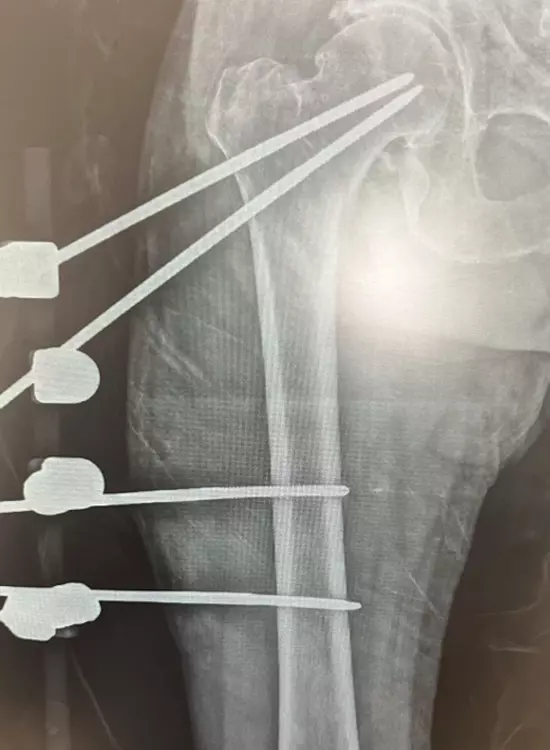

Ortopedia y Traumatología

Galería

Galería y Medios